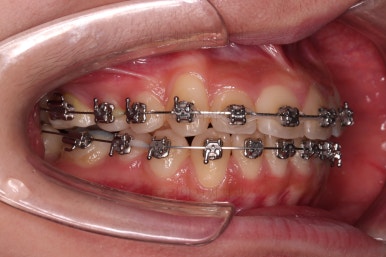

가지런하게 한 이후에는 자칫 비발치 교정이라 생길 수 있는 돌출입이라던지 뻐드러짐 등을 체크해 주고 원하시는 바와 연산동치과 의견을 종합하여 추후의 방향을 다시금 의논하게 됩니다.

약간의 뻗침과 아랫니에 비해 아주 약간 나와있는 앞니를 말씀하셨기 때문에 가능한 방법을 제시하고 치료를 이어갑니다.

입시로 해둔 치아는 잘 버티고 있네요.

보통 뒤로 당겨야 할 양이 많다면 미니스크류를 사용하는데, 이번 환자분은 그정도 까지는 아니어서 최대한 철사 자체에 힘을 주고 뺐다꼈다 하는 고무줄을 사용하며 치료를 마무리하기로 했어요.